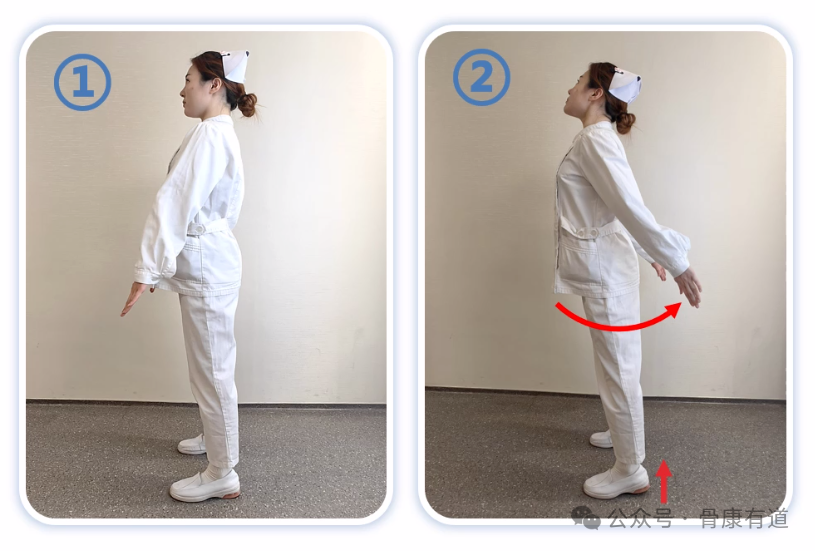

动作一:

①自然站立,双脚分开与肩同宽;

②踮起脚跟,同时抬头向上看,两臂伸直、掌心向后推出,尽量伸展腰背部,坚持3秒后复原,还原时缓慢呼气。①-②动作为一组,重复10次。注意踮脚抬头伸展时吸气,感受腰背部肌肉紧绷。